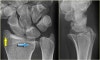

X-ray : 콜레스골절(Colle’s fracture)

X-ray : 척골 경상돌기 골절(Ulnar styloid process fracture)